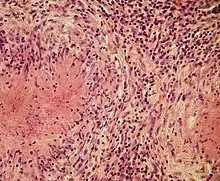

Structurally, epithelioid cells (when examined by light microscopy after stained with hematoxylin and eosin), are elongated, with finely granular, pale eosinophilic (pink) cytoplasm, and central, ovoid nuclei (oval or elongate), which are less dense than that of a lymphocyte.[4] They have indistinct shape and often appear to merge into one another, forming aggregates known as giant cells. When examined by transmission electron microscopy in epithelioid cells in the field of Golgi lamellar complex are taped not only zonated, but also sleek vesicles with dense center, and also great many (more than 100) large granulas with diameters up to 340 nm and with finegranular matrix more light than in macrophage granulas, sometimes with perigranular halo. “The most prominent feature of these cells is the enormous Golgi area; up to 6 individual stacks of Golgi cisternae may be present as well as a few bristle-coated and numerous smooth vesicles”.[5][4] Epithelioid cells have tightly interdigitated cell membranes in zipper-like arrays that link adjacent cells.[3] This cells are central in the formation of granulomas, which are associated with many serious diseases.[4] In granulomas, epithelioid cells perform the functions of delimiting.[3]